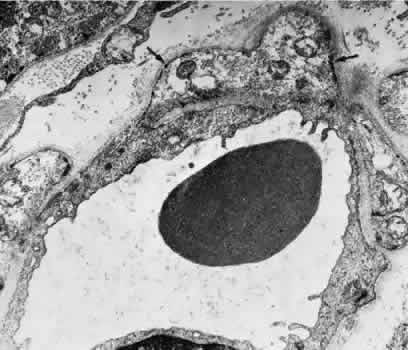

The capillaries and venules of the ciliary body are 15 to 30 μm in diameter and are fenestrated in both the pars plicata and pars plana. They closely resemble the capillaries of the choriocapillaris except that they are smaller. The fenestrae of these vessels range in size from 300 to 1,000 nm in diameter.64 The major difference between the capillaries in different areas of the ciliary body is that only those of the pars plana are in contact with the elastica of Bruch's membrane on the surface facing the pigmented epithelium. The capillaries present in the ciliary muscle are nonfenestrated (Figs. 16 and 17). The blood vessels are innervated by small branches of sympathetic fibers.

Fig. 16. Electron micrograph of a portion of a capillary facing the stroma of the ciliary process. The endothelial cell contains moderate amounts of rough-surfaced endoplasmic reticulum and numerous pinocytotic vesicles and few fenestrae. A very thin basement membrane is present. Particles of thorium dioxide may be seen in the lumen (l). This specimen was taken from a rat.

Fig. 17. Electron micrograph of a portion of a capillary from the ciliary process facing the pigmented epithelium (p). Note the absence of an elastic lamina between the vessel and the pigmented epithelium. Fenestrae are present, and the endothelium is quite attenuated. This specimen was taken from a rat injected with thorium dioxide. l, capillary lumen.